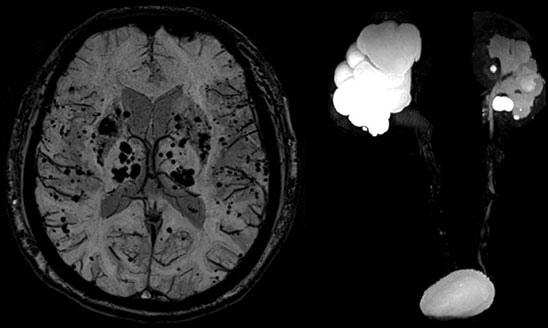

MAGNETOM Spectra 3.0T新一代聚能光谱磁共振

MAGNETOM Spectra 3.0T聚能光谱磁共振